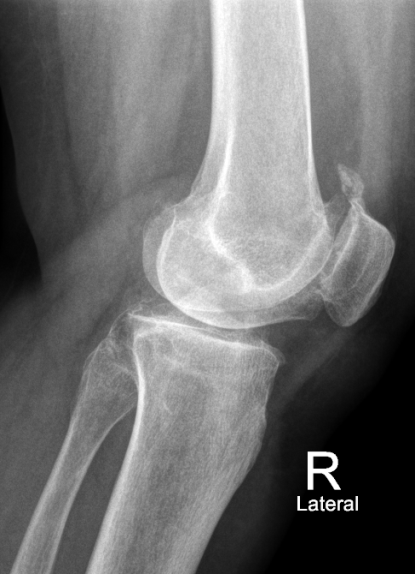

Правосторонний посттравматический гонартроз Rg III ст. Сросшийся перелом правой бедренной кости в условиях синтеза стержнем.

После тотального цементного эндопротезирования коленного сустава эндопротезом Sigma CR.